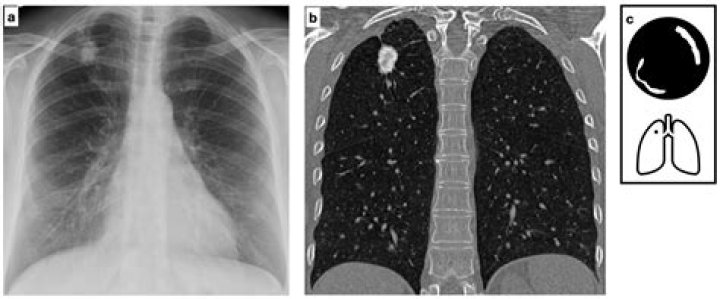

In general, malignant calcified granulomas double in size every one to six months. Nodules with a slower or faster growth rate are less likely to be cance...